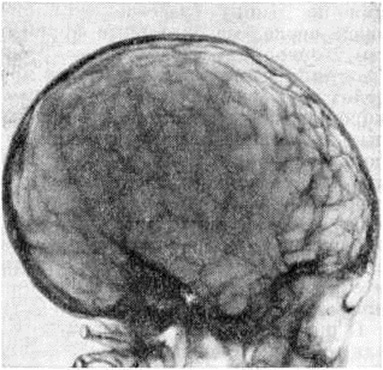

Рис 2.

Характерный внешний вид при краниостенозе (башенныи череп).

Диагноз, как правило, не представляет особых затруднений. Характерный внешний вид больного с необычной формой черепа (рисунок 2) и данные рентгенологическое обследования позволяют установить диагноз без дополнительных исследований. Рентгенологические исследование черепа при Краниостеноз направлено в первую очередь на выявление признаков преждевременного заращения швов и деформаций черепа.

Повышение внутричерепного давления проявляется на краниограммах (рисунок 3) истончением костей свода, усилением рисунка пальцевидных вдавлений (симптом кованого серебра»), углублением борозд синусов, образованием дополнительных венозных выпускников, изменением турецкого седла и расхождением необлитерированных швов.

Рентгенограмма черепа в боковой проекции (краниограмма) при краниостенозе: выраженное истончение костей свода черепа с усиленными пальцевидными вдавлениями.